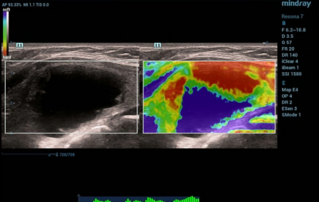

Female pelvic floor anatomy, which developed since the early 20th century, has had a variety of theories, including integral theory, three levels of vaginal support theory, "hammock hypothesis", and three-chamber system. Supporting structures such as pelvic floor muscles, fascia and ligament play an important role in maintaining the normal function of pelvic floor, among which levator ani muscle group is one of the most important supporting structures.